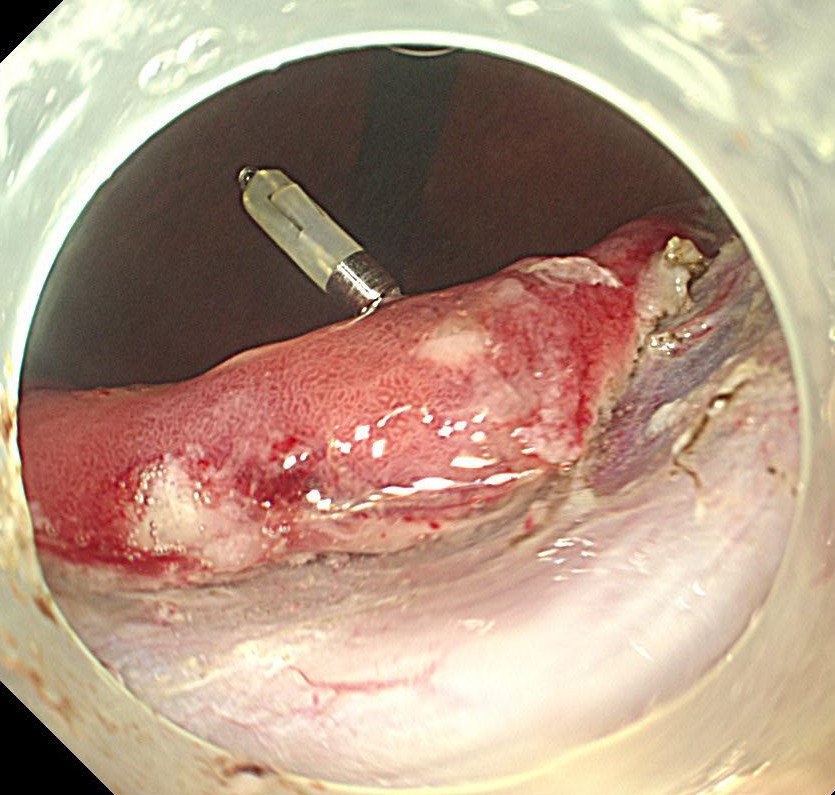

胃角小弯前壁に中心陥凹 周囲隆起するIIA+IIC早期胃がんを認めます。腫瘍径は30mmとやや大きな腫瘍です。

NBI(狭帯域光観察)で腫瘍の不整な新生血管が認識されます。